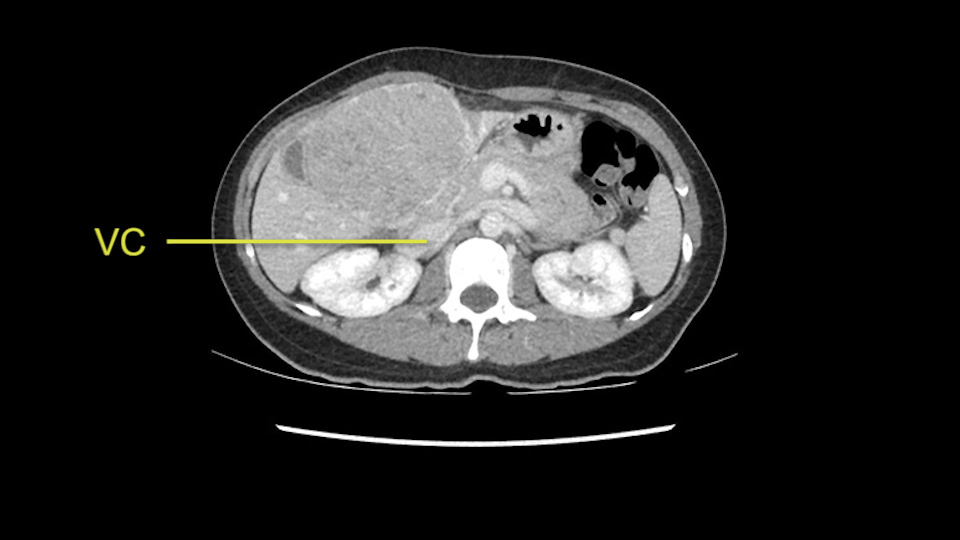

When you see the axial sections of the scan, you find it's a largely exophytic mass and its well-encapsulated. So this is typically true of a well-differentiated hepatocellular carcinoma. If you look at this, this is the gallbladder which is being displaced to the right and the mass is in the Sg4 of the liver, exophytic, projecting down. As it is coming down, it is also displacing the duodenum and the head of the pancreas which is being pushed towards the left and it's going right up to the cava, the start of the anterior surface of the cava. Obviously getting a lot of collaterals and vascularity from all the vessels around but one has to be very careful in evaluation of the main portal pedicle in this particular case and of course arterial inflow to the Sg4 and of course the left lobe of the liver.

Now let’s look at some specific anatomical points for planning this surgery. First thing you see when you see a left hemihepatectomy is that where is the left portal vein and the right portal vein branching? And what is the stump of the left portal vein available for you for ligation? In this particular case, you’ll find that there’s overhanging of the tumor but left portal vein pedicle is sufficiently available for us for ligation.

The cava however is again displaced by this well encapsulated mass, so I would expect that I should be able to lift out of the cava with some moment of careful dissection and the cava is not infiltrated by this tumor. Most of the tumor is below the portal plane and the hepatic-venous vein is completely free. You have the left and the middle hepatic vein joining together and opening up. The right hepatic vein is as usual. All the superior segments of the liver are intact so we do not expect any major problem in this particular case as far as the venous outflow is concerned. So this is about the preoperative planning as far as this case is concerned.

So in planning for this operation, as I look at the scans, I first visualize the arterial phase and I can see that there’s are a lot of big feeding arteries to this large tumor. Likely all the right side vessels feeding the right side of the liver: right hepatic artery and likely the Segment 4 artery are spared from the tumor. It’s likely the left hepatic artery is ramificating and giving feeding arteries to this tumor. It certainly looks like a large mass that its compressing other structures like the cava, the pancreas, the stomach; but I think there’s a plane and we can see that better in the venous phase. There’s a plane of separation between the gallbladder, the pancreas, the cava, that this tumor is abrupting but likely not invading. Usually, these masses actually don’t invade at that level and basically are pushing the tissues and once you open, you’re able to separate the tumor. Sometimes there’s some adhesions but you can actually separate and there’s usually no invasion.